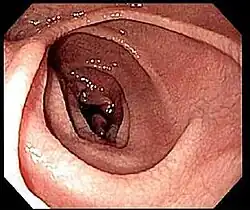

Si la sérologie est positive, une endoscopie de l'intestin grêle avec biopsies sera pratiquée. La fibroscopie peut montrer des anomalies non spécifiques : aspect en mosaïque, plis raréfiés de la muqueuse[56]…

Même en cas de normalité de l'aspect, une confirmation doit être faite par biopsie de la muqueuse duodénale. Elle doit être multiple (4 à 6 échantillons[43]) en raison d'une atteinte pouvant être partielle.